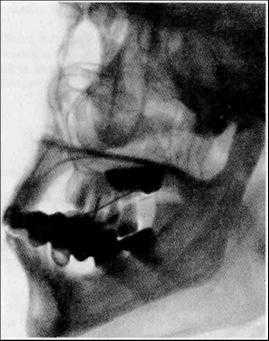

- Снимки обычно выполняют в 5 проекциях: правой и левой боковой, переднезадней (проекция Тауна), заднепередней (проекция Колдуэлла) и аксиальной.

Рентгенографию черепа часто применяют для диагностики переломов основания или свода. Однако перелом основания черепа может остаться нераспознанным при высокой плотности костей. Исследование позволяет выявить врожденные аномалии развития черепа, а также увеличение размеров, эрозии или остеопороз турецкого седла, обусловленные повышением внутричерепного давления (ВЧД). Выраженная внутричерепная гипертензия (ВЧГ) может сопровождаться увеличением размеров головного мозга, который давит на внутреннюю пластинку черепа, оставляя на ней характерные знаки ("пальцевые вдавления"). При остеомиелите рентгенография черепа позволяет выявить очаги кальцификации костей черепа, при хронической субдуральной гематоме - внутричерепные кальцификаты. Кроме того, с помощью данного метода можно либо непосредственно диагностировать обызвествленные опухоли головного мозга (например, олигодендроглиомы или менингиомы), либо судить о наличии внутричерепных объемных образований по смещению обызвествленного шишковидного тела относительно срединной плоскости черепа. И наконец, на рентгенограммах черепа можно выявить другие изменения костных структур, характерные для метаболических нарушений (например, при акромегалии или болезни Педжета).